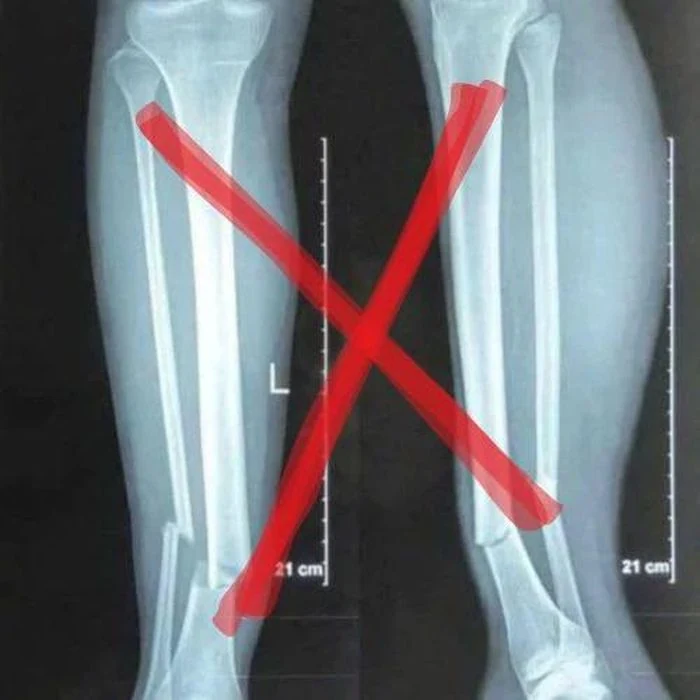

Nguyễn Xuân Son vừa nhập viện, “nhanh như chớp” đã lan truyền phim chụp xquang giả

Xuân Son vừa nhập viện đã có phim x quang “fake” tung lên khiến nhiều người hốt hoảng.